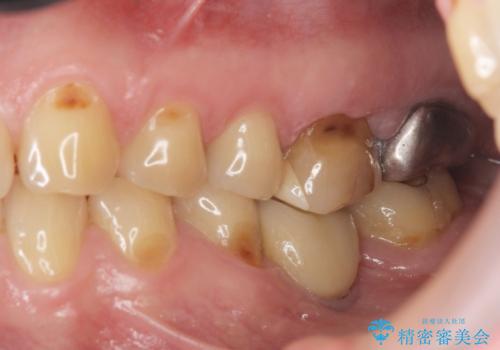

- 半年前から奥歯から嫌な臭いがする、と治療を求めて来院されました。

銀歯を除去したところ、虫歯が大きく再発しこのままではかぶせ直しができないような状況でした。

・深い虫歯 →歯周外科を行うことで歯ぐきの腫れを改善

・根尖性歯周炎 →精密根管治療

・咬合機能の回復 →セラミッククラウンの製作

と問題点を一つづつ丁寧に解決し、長期的に虫歯が再発せず安定を見込める治療を行っていきます。